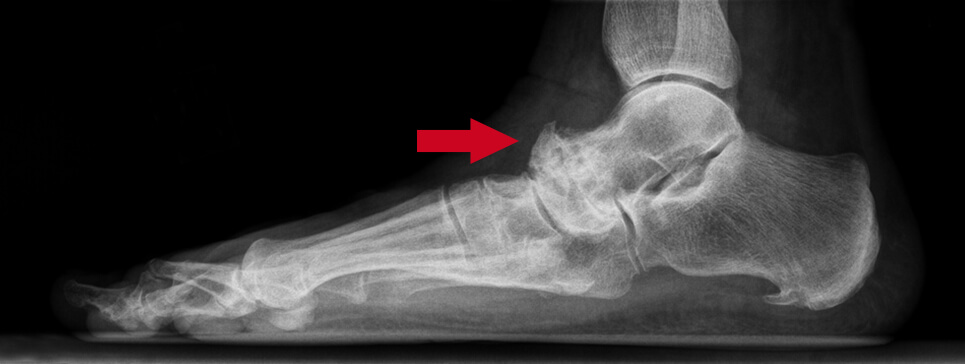

Op basis van de klachten, medische geschiedenis en lichamelijk onderzoek van de patiënt kan vaak al veel duidelijkheid worden verkregen. Omdat er verschillende gewrichten dicht bij elkaar liggen rondom de enkel, kan het voor de patiënt moeilijk zijn om te bepalen welk gewricht precies de oorzaak is van de klachten. Een röntgenfoto biedt meestal goede zichtbaarheid om te bepalen of er sprake is van slijtage en welk(e) gewricht(en) zijn aangetast. In sommige gevallen kan een CT-scan nodig zijn om de diagnose met meer zekerheid te stellen. Een echo kan worden gebruikt om artroseverschijnselen te detecteren langs de gewrichtsranden.